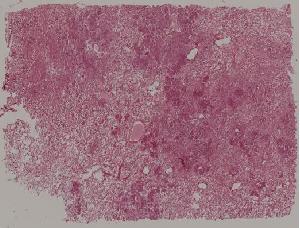

66.活动性结节性肝硬化

67.非活动性结节性肝硬化

68.胆汁性肝硬化

69.肝细胞性肝癌